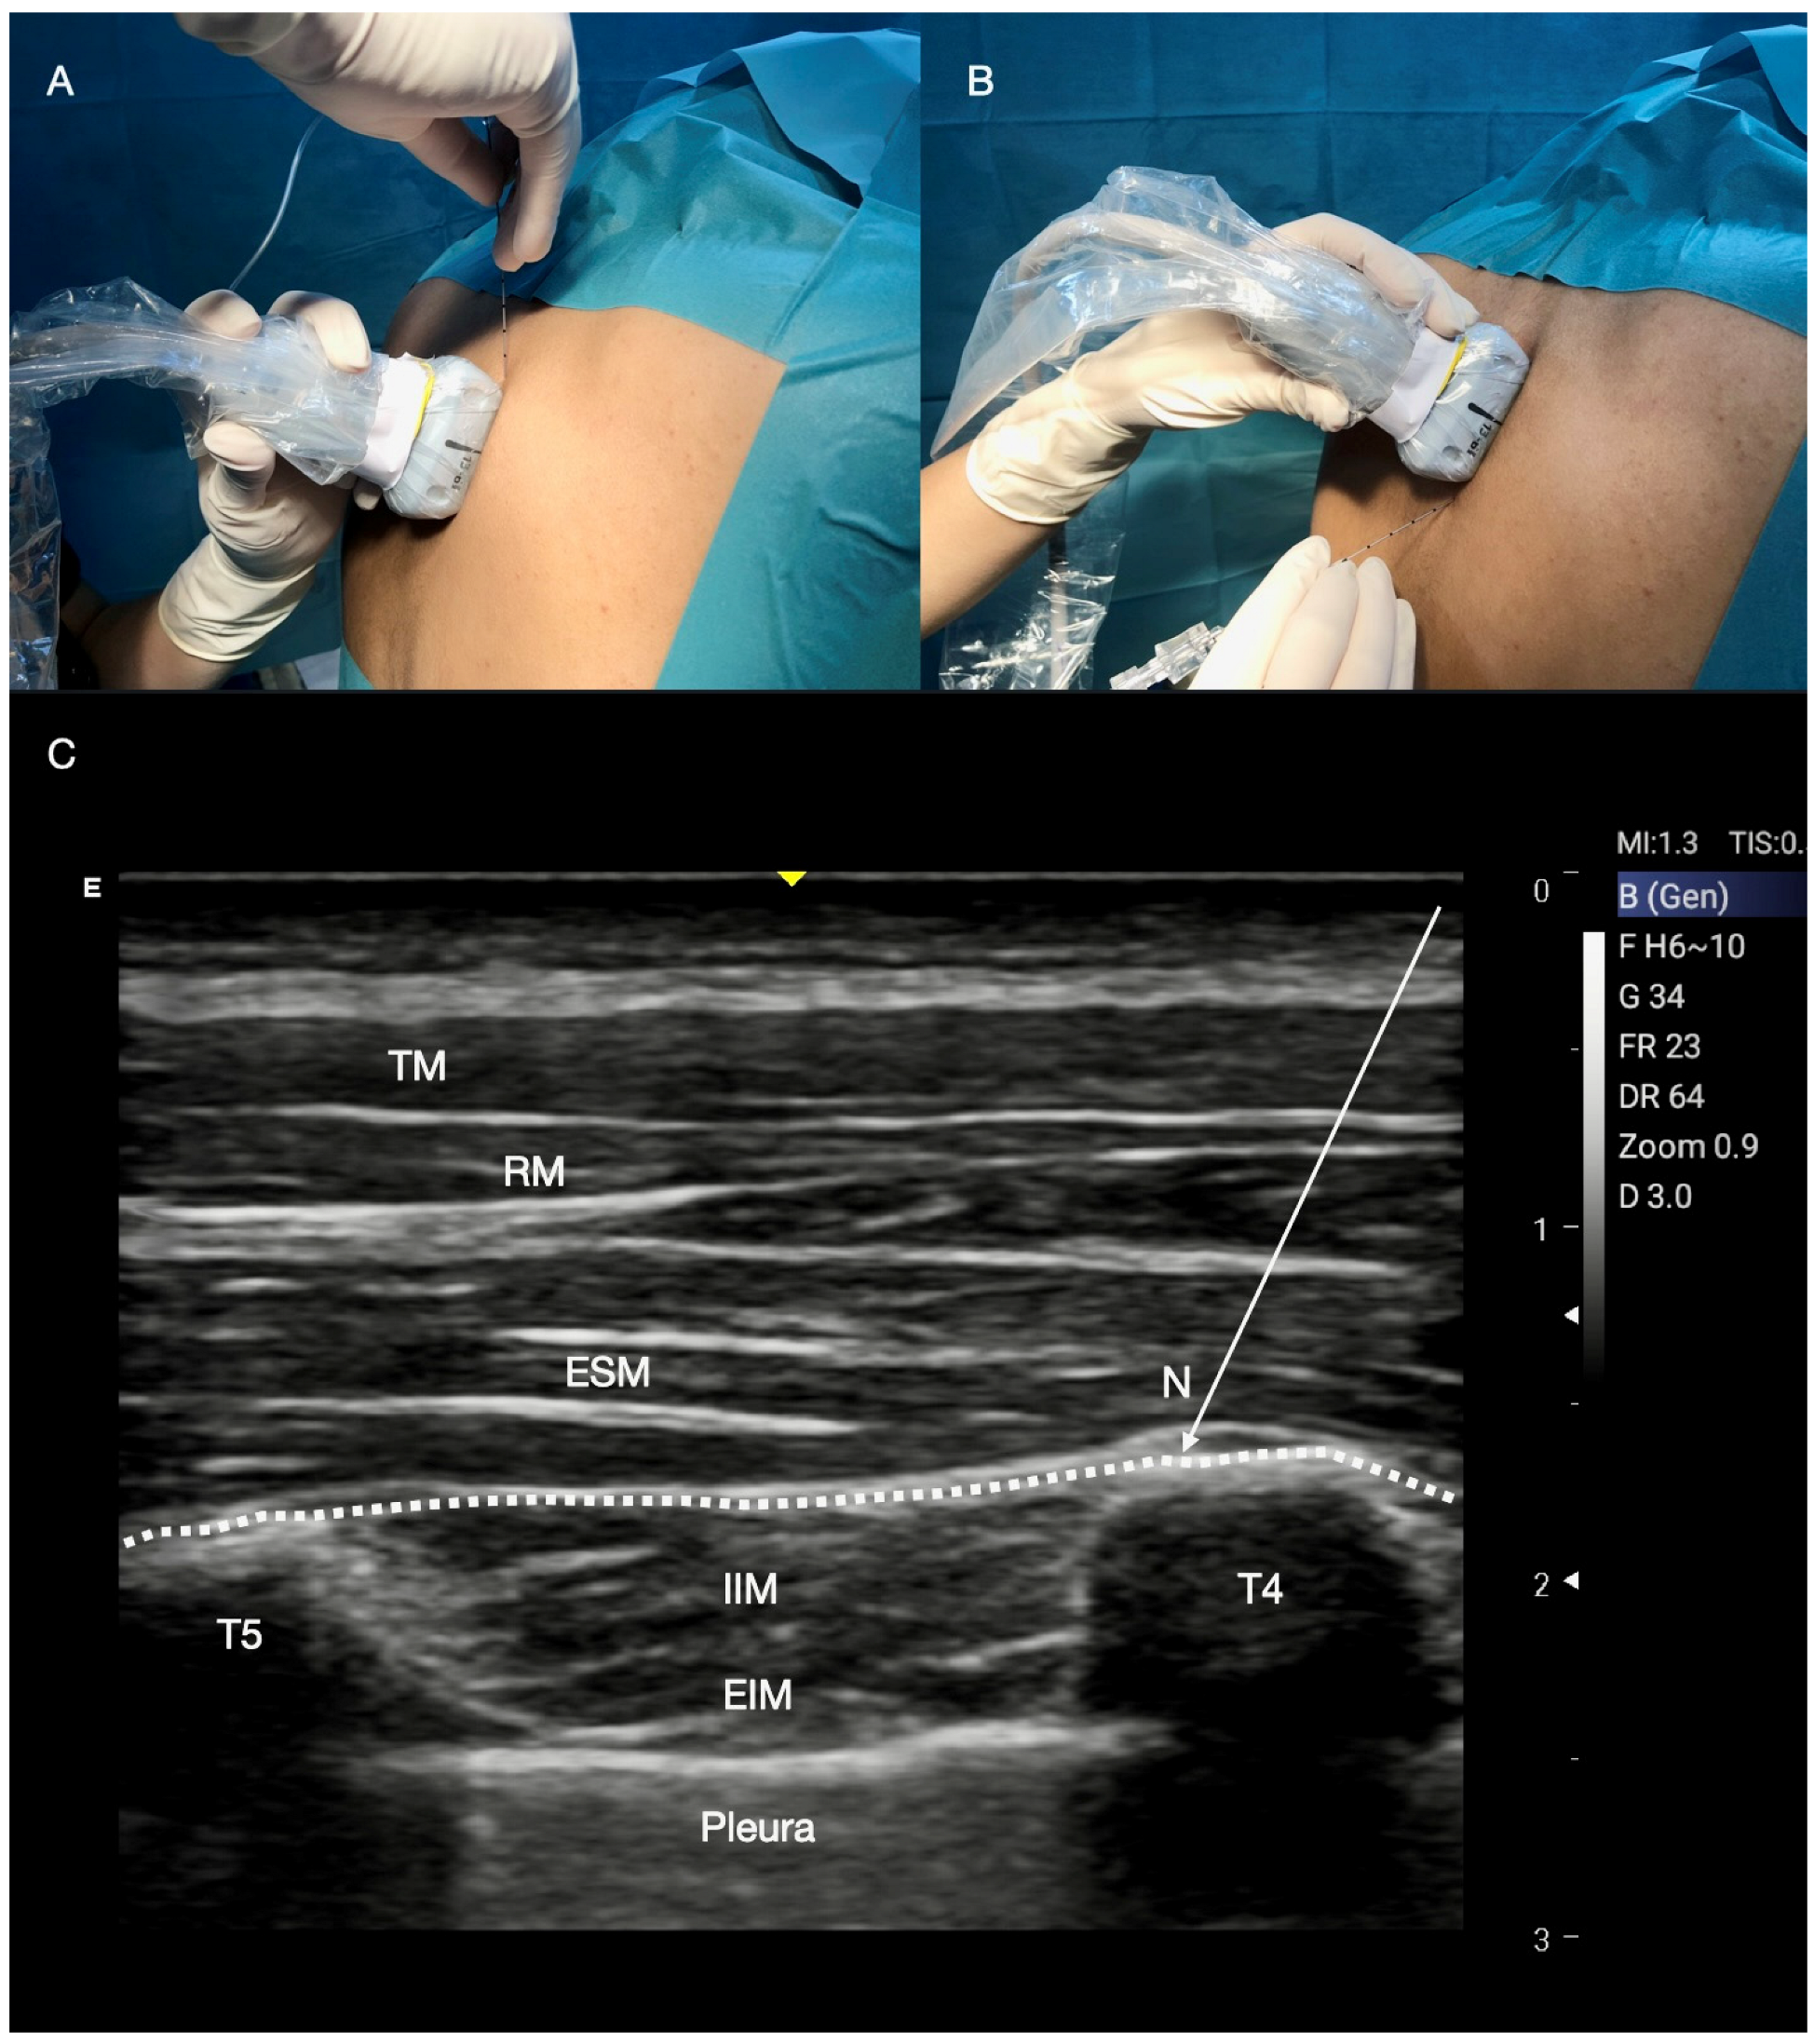

2.5. Erector Spinae Plane Block

Technique for ESP Block

| ESP | Cardiac surgery with mini-thoracotomy, open thoracotomy, rib fractures after mini-thoracotomy, chronic post thoracotomy pain syndrome. | Ventral rami of the spinal nerves. Dorsal rami when LA spreads into the paravertebral space. Posterior and lateral thoracic wall. Intercosto-brachial nerve. Between erector spinae muscle and T4–T5 transverse processes. 20–25 mL of LA. | The rib has a convex ultrasound shape, while the transverse process has a squared ultrasound shape. An effective ESP block is realized when the ultrasound erector spinae muscle lift is observed during the injection of LA |